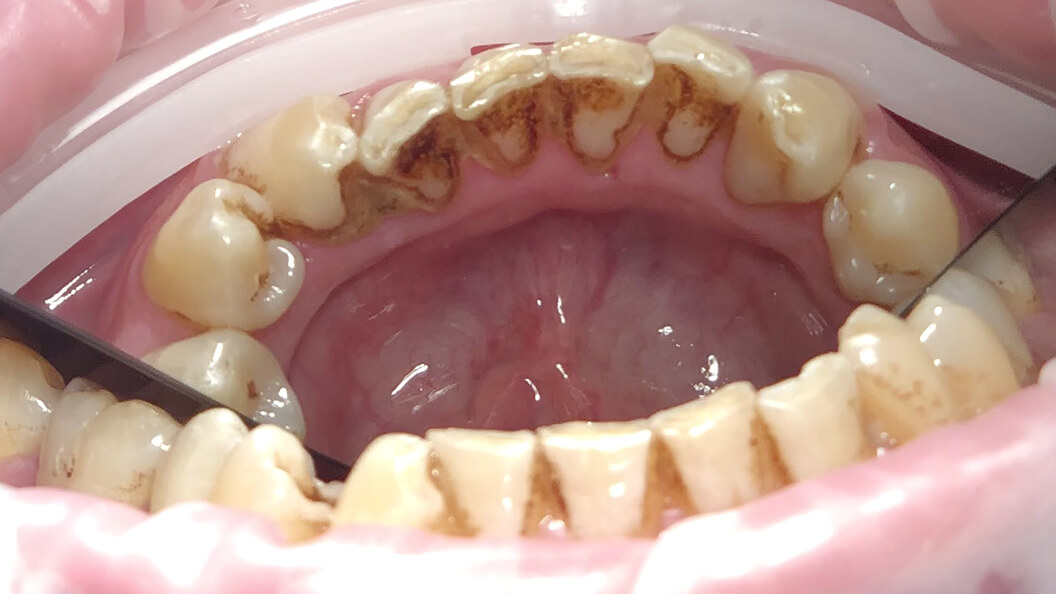

Фото пациента во время профессиональной чистки зубов Prophyflex

Профессиональная чистка зубов Prophyflex

В «Стоматологии Комфорта» предлагаем бережную чистку зубных отложений по немецкой системе ProphyFlex (Профифлекс) от компании KaVo Dental Excellence. Мягкий зубной налет и пигментацию эмали вычищаем за 1 посещение. Сеанс длится 30 минут. Технология бережно воздействует на зубы, не повреждая зубную эмаль.

Примеры работ